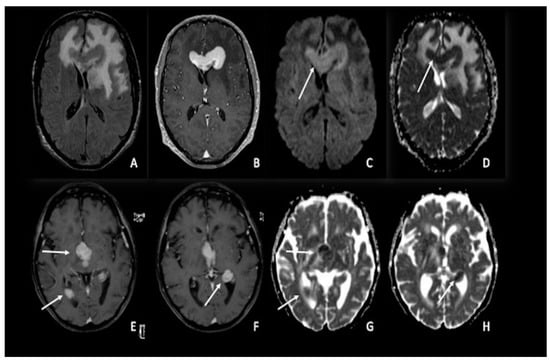

6. Meningiomas and Vestibular Schwannomas